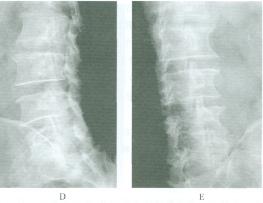

臨床表現無特異性診斷主要依據X線平片,包括正、側位,左、右斜位及伸屈動力位片。對有疑問的病例應行斷層攝片,從而更清楚地顯示病變部位。CT和MRI檢查對診斷本病僅提供參考但有助於鑑別與發現其他疾患。本病的X線片特點為(圖1):

1.頸椎關節突間部有分界清晰的裂隙,斷端邊緣硬化、變鈍。

3.椎弓後半部向後脫位,椎體向前輕度滑脫(≤Ⅰ度),椎間孔可變小。

4.多合併同側或相鄰的椎弓根、關節突發育不良以及脊柱隱裂等其他畸形

值得注意的是,在CT掃描切層上,頸椎椎弓裂與腰椎峽部裂表現不盡相同,其主要表現為關節突與椎體相連部位連續性中斷,斷端光滑,關節突與椎體的夾角也不同。